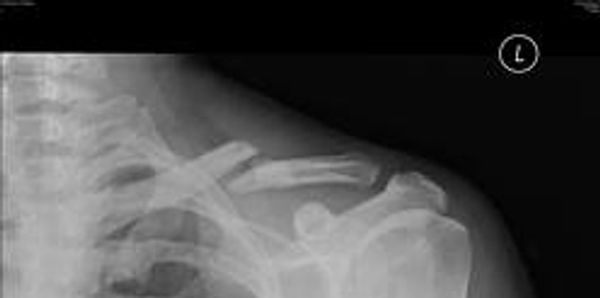

The closed fracture is another common fracture among children, the collar bone is a bone that tends to break. one reason for this it that when a child falls they place their hands in front of them, a shock wave is sent up the arms and the collar bone snaps under the pressure.